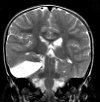

Пункция кисты головного мозга. Диагностическая операция, при которой нейрохирург входит в кисту специальной иглой, чтобы взять образец жидкого содержимого. Вмешательство проводится для последующего лабораторного исследования полученной жидкости, введения контрастного или в терапевтических целях. Пункция кисты головного мозга показана пациентам с недавно диагностированной патологией, проводится для выяснения характера патологического процесса, определения размеров и расположения кисты перед хирургическим удалением, снижения давления жидкости на окружающие ткани головного мозга. Выполняется в плановом порядке в условиях отделения нейрохирургии.

Обычно в неврологии вмешательство назначают пациентам с недавно диагностированной кистой головного мозга, без травм, кровотечений или хирургических вмешательств. Поскольку киста образуется на месте мертвых клеток головного мозга, необходимо определить исход гибели нейрона. Ответ на этот вопрос может быть дан только путем изучения содержимого кисты, во время которой проводится дифференциация формирования воспалительного генеза и кисты, которая является частью опухоли. Если киста находится в продолговатом мозге, исследование ее содержимого позволяет выявить или устранить сирингомиелию.

Введение контрастной среды в кисту во время ее пункции с последующей МРТ головного мозга выполняется для точного определения положения кисты и оценки ее размера. Эти данные необходимы нейрохирургу для планирования операции. Результаты контрастирования и анализа содержимого кисты позволяют уточнить показания к ее хирургическому лечению и выбрать наиболее приемлемый метод ее удаления. Процедура вмешательства похожа на укус абсцесса и подробно описана здесь. Подготовка пациента, облегчение боли, противопоказания и осложнения подробно описаны здесь.